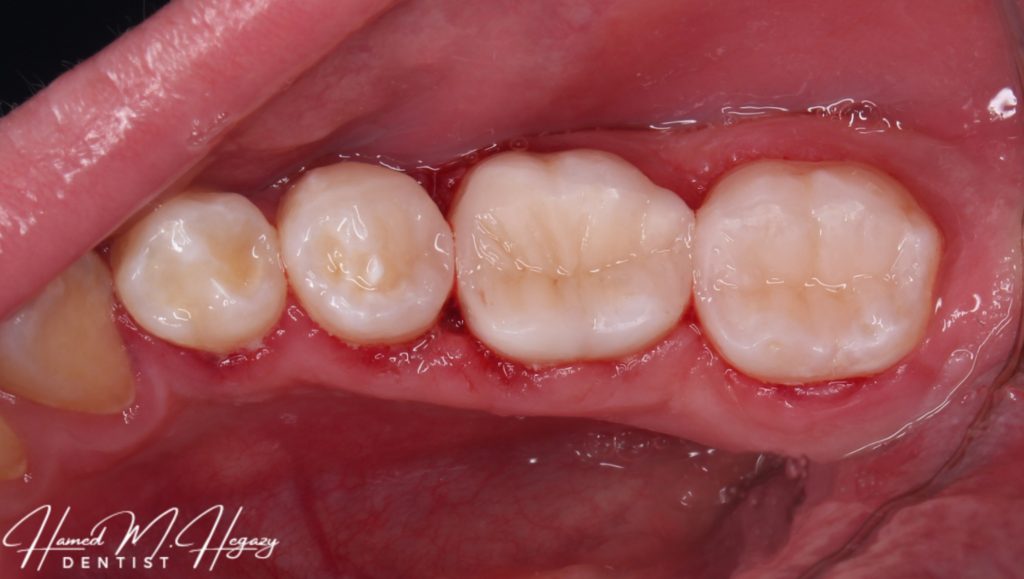

Pre-operative

Final look